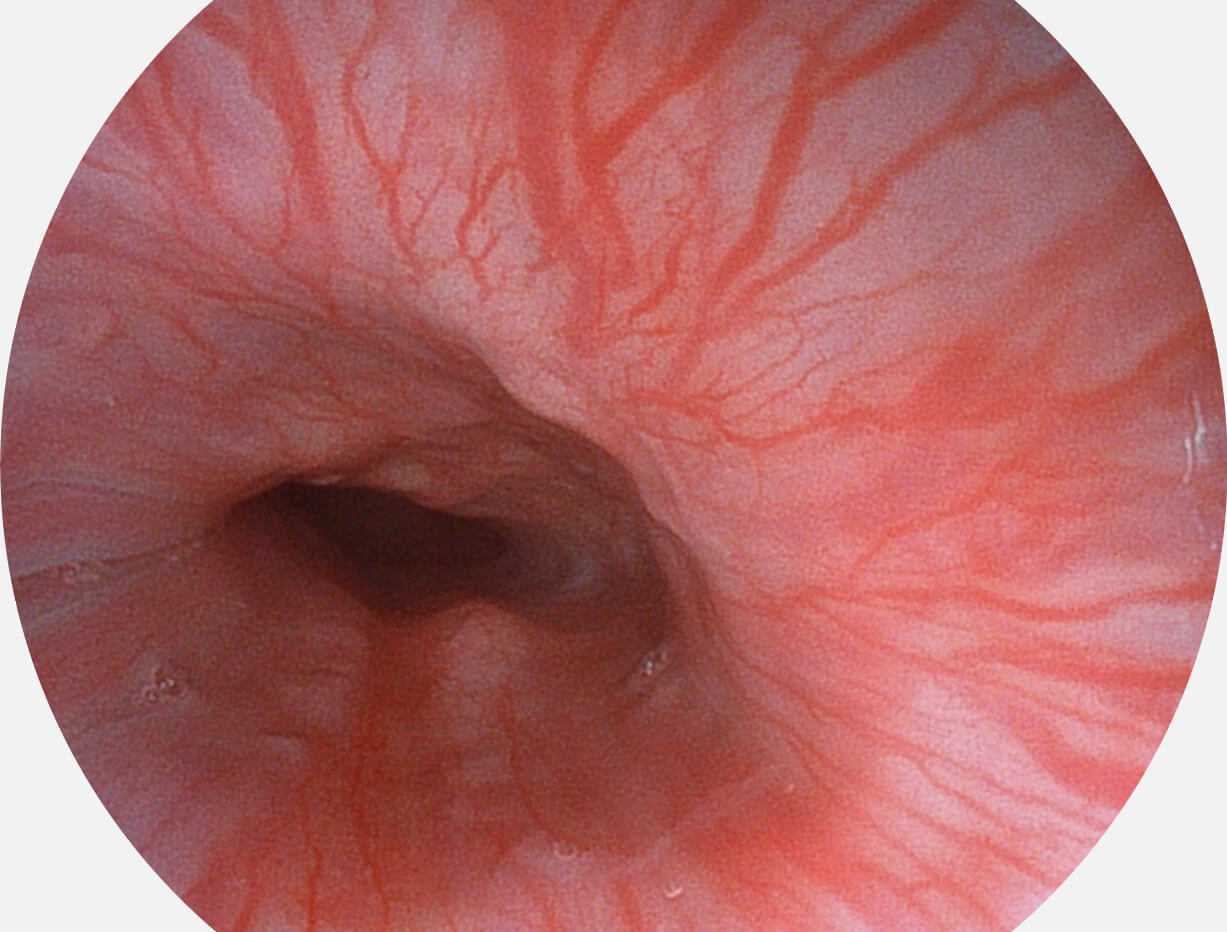

白光图像

VIST图像

Versatile Intelligent Staining Technology, VIST

强调浅层黏膜结构的同时,保证照明亮度和提升浅层微血管与中层血管颜色对比度,病变边界更清晰。